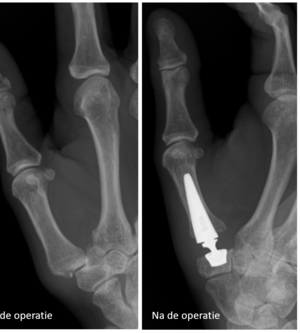

Duimbasisprothese